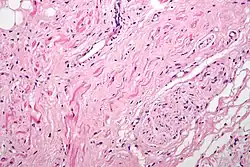

Микрофотография синусового узла. Мышечные волокна в узле напоминают миоциты сердца, однако они тоньше, имеют волнистую форму и менее интенсивно окрашиваются гематоксилин-эозином. На фотографии к узлу прилегает нервное волокно: синусовый узел взаимодействует с ответвлениями блуждающего нерва.

Клетки, составляющие синусовый узел, гистологически отличаются от клеток рабочего миокарда. Хорошим ориентиром служит выраженная a.nodalis (узловая артерия). Клетки синусового узла по размерам меньше клеток рабочего миокарда предсердия. Они группируются в виде пучков, при этом вся сеть клеток погружена в развитый матрикс. На границе синусового узла, обращенной к миокарду устья верхней полой вены, определяется переходная зона, которая может расцениваться как присутствие клеток рабочего миокарда предсердий в пределах синусового узла. Такие участки вклинения клеток предсердия в ткань узла чаще всего встречаются на границе узла и пограничного гребня (выступа стенки правого предсердия сердца, которым заканчиваются вверху гребенчатые мышцы)[1].

Гистологически синусовый узел состоит из т. н. типичных клеток узла. Они располагаются беспорядочно, имеют веретенообразную форму, а иногда разветвления. Для этих клеток характерно слабое развитие сократительного аппарата, случайное распределение митохондрий. Саркоплазматический ретикулум развит хуже, чем в миокарде предсердий, а система T-трубочек отсутствует. Это отсутствие, правда, не является критерием, по которому выделяются «специализированные клетки»: часто система T-трубочек отсутствует и в рабочих кардиомиоцитах предсердия.

По краям синусового узла наблюдаются переходные клетки, отличающиеся от типичных лучшей ориентацией миофибрилл наряду с более высоким процентом межклеточных соединений — нексусов. Находимые ранее «вставочные светлые клетки», по последним данным, являются не более чем артефактом.